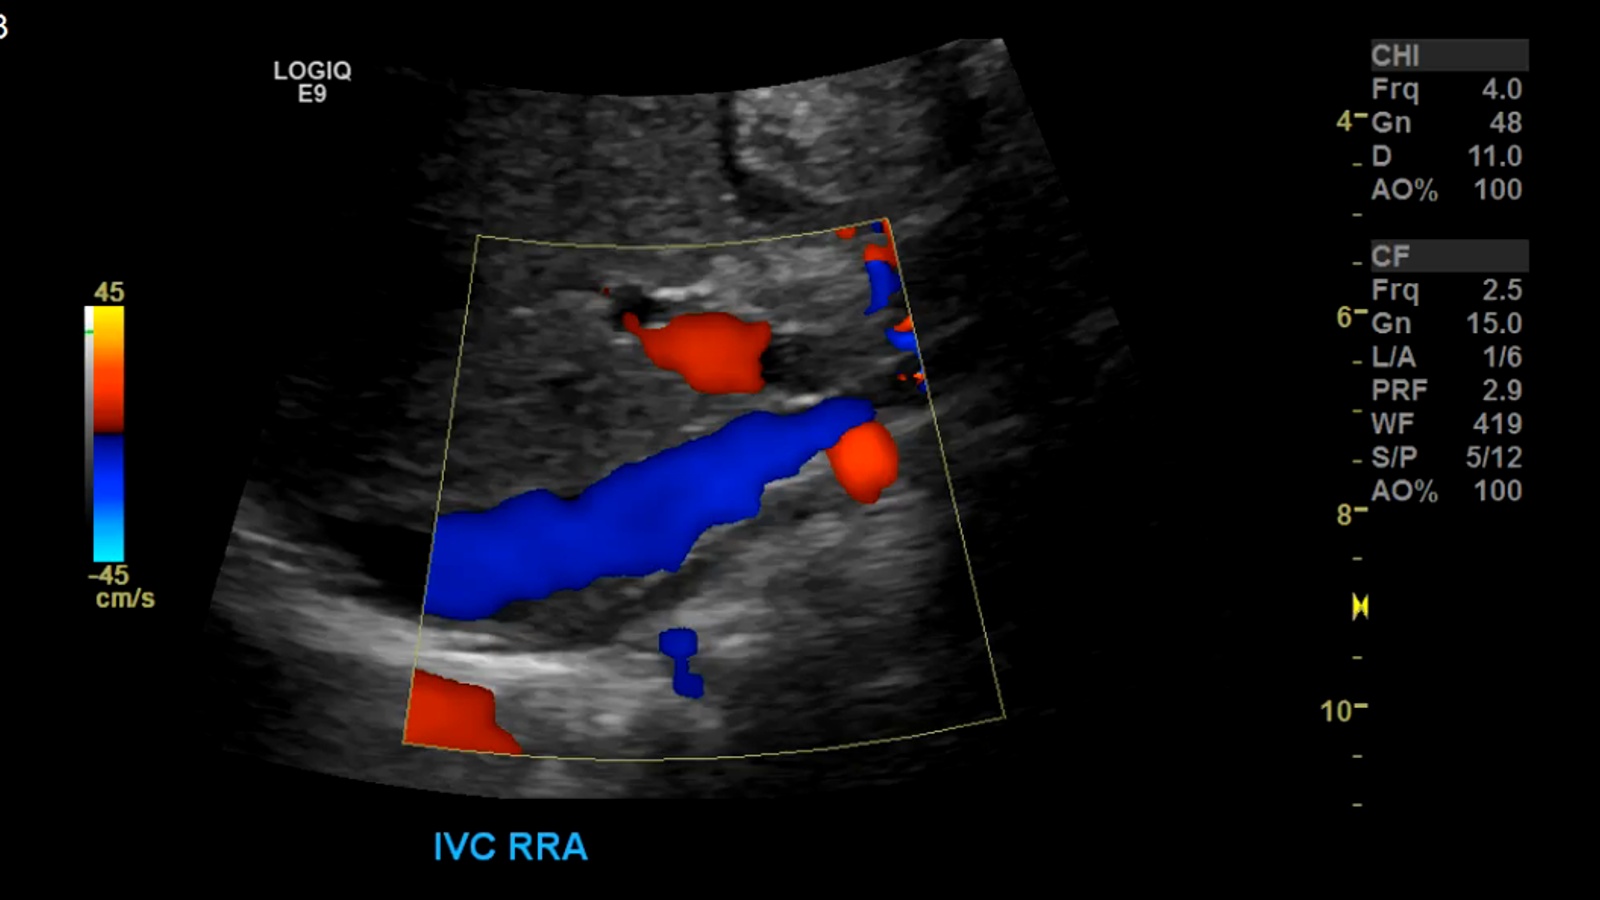

image11